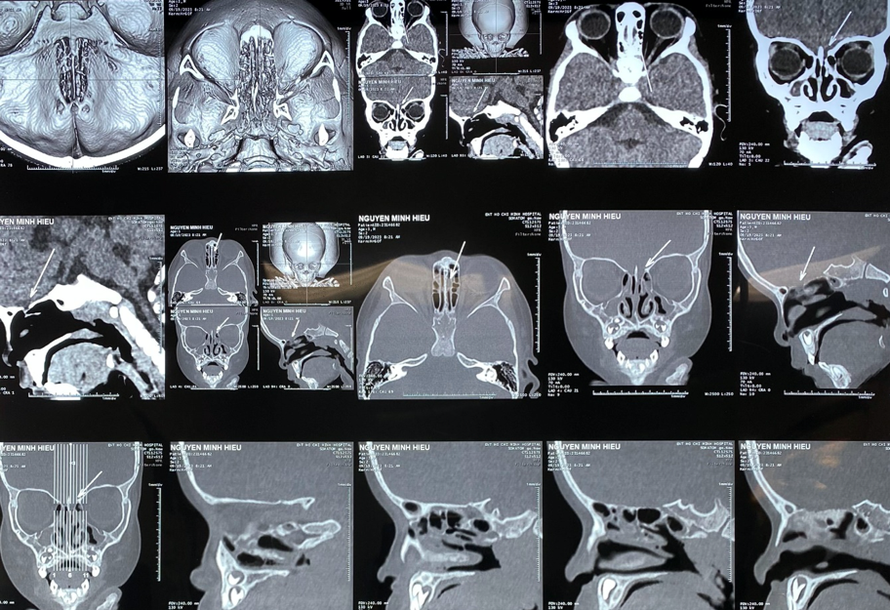

(Ngày Nay) - Bệnh viện Tai Mũi Họng TP.HCM vừa phối hợp phẫu thuật vá rò dịch não tuỷ cho bé trai 3 tuổi (ở Định Quán, Đồng Nai) bị tổn thương do đũa ăn chọc vào mũi trong lúc chơi.

Theo bác sĩ Nguyễn Minh Hảo Hớn, trưởng khoa Mũi Xoang bệnh viện Tai Mũi Họng TP.HCM, hơn một tháng trước, bé N.M.H trong lúc cầm đũa ăn chạy loanh quanh trong nhà thì bị ngã, đũa chọc vào mũi. Bé tự rút ra khỏi mũi, máu tự cầm nên người nhà không đưa đi thăm khám.

Khoảng hai ngày sau, bé H. bị sốt, phụ huynh đưa đến phòng khám tư rồi sang bệnh viện tỉnh điều trị. Bé được chẩn đoán viêm màng não, được điều trị hai tuần rồi xuất viện. Tuy nhiên, bé vẫn tiếp tục chảy dịch ở mũi.

Người nhà lo lắng nên đưa con đến Bệnh viện Tai Mũi Họng TP.HCM khám. Các bác sĩ tại đây chẩn đoán bé bị rò dịch não tuỷ sau chấn thương, viêm màng não (đã điều trị ổn).

Bệnh viện đã liên hệ mời các bác sĩ khoa ngoại thần kinh Bệnh viện Nhi Đồng 2 hội chẩn và phẫu thuật vá bít lại lỗ rò dịch não tuỷ, lấy mỡ bụng lấp vào vị trí tổn thương và sử dụng kháng sinh, kháng viêm trong khoảng 7-10 ngày... Sau phẫu thuật, bé H. tỉnh táo, tự đi lại, vui chơi, không còn nhức đầu và chảy dịch mũi.

Sau chấn thương, người nhà nên đưa bé đến bệnh viện khám ngay để phát hiện tổn thương sàn sọ và điều trị sớm tránh tình trạng viêm màng não. Vá rò dịch não tuỷ qua đường nội soi mũi xoang bằng phương pháp nhiều lớp mang lại thành công cao, hậu phẫu nhẹ nhàng, ra viện sớm, không để lại di chứng.